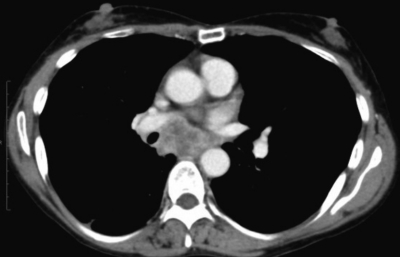

検査所見:血液所見:赤血球 350 万、Hb 9.8 g/dL、Ht 30 %、白血球 10,300、血小板 30 万。血液生化学所見:AST 19 U/L、ALT 15 U/L、LD 158 U/L (基準 176〜353)、γ-GTP 16 U/L (基準 8〜50)、総ビリルビン 0.4 mg/dL、総蛋白 7.2 g/dL、アルブミン 3.8 g/dL、尿酸 2.9 mg/dL、尿素窒素 11 mg/dL、クレアチニン 0.5 mg/dL、 Na 140 mEq/L、 K 4.0 mEq/L、 Cl 105 mEq/L、 Ca 8.9 mg/dL、Fe 20 μg/dL、TIBC 231 μg/dL (基準 290〜390)、フェリチン 643 ng/mL (基準 20〜120)、CEA 4.5 ng/mL (基準 5以下)。CRP 1.4 mg/dL。画像所見:上肺野(肺野条件)、中肺野(縦隔条件)、下肺野(肺野条件)及び上腹部の造影CTを別に示す。呼吸機能所見:現在と 20 歳時の膝蓋骨骨折手術前のフローボリューム曲線を別に示す。